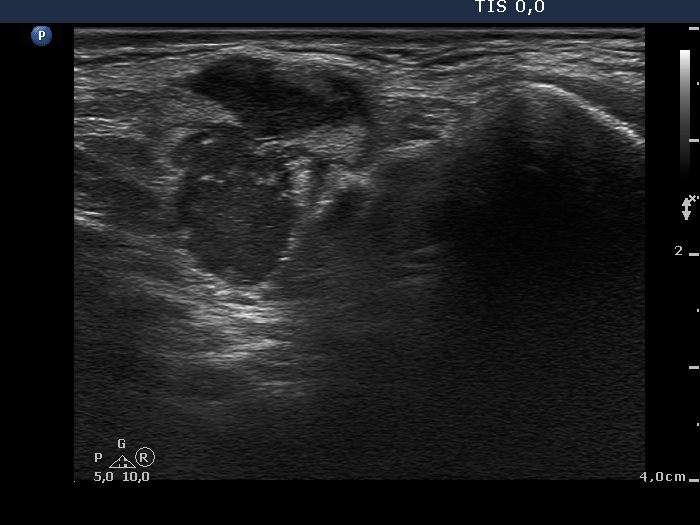

Ultrasonography: the thyroid was intact. There were multiple nodes in both supraclavicular regions. The nodes presented an absolutely irregular shape and border. They contained numerous hyperechogenic circumscribed areas.